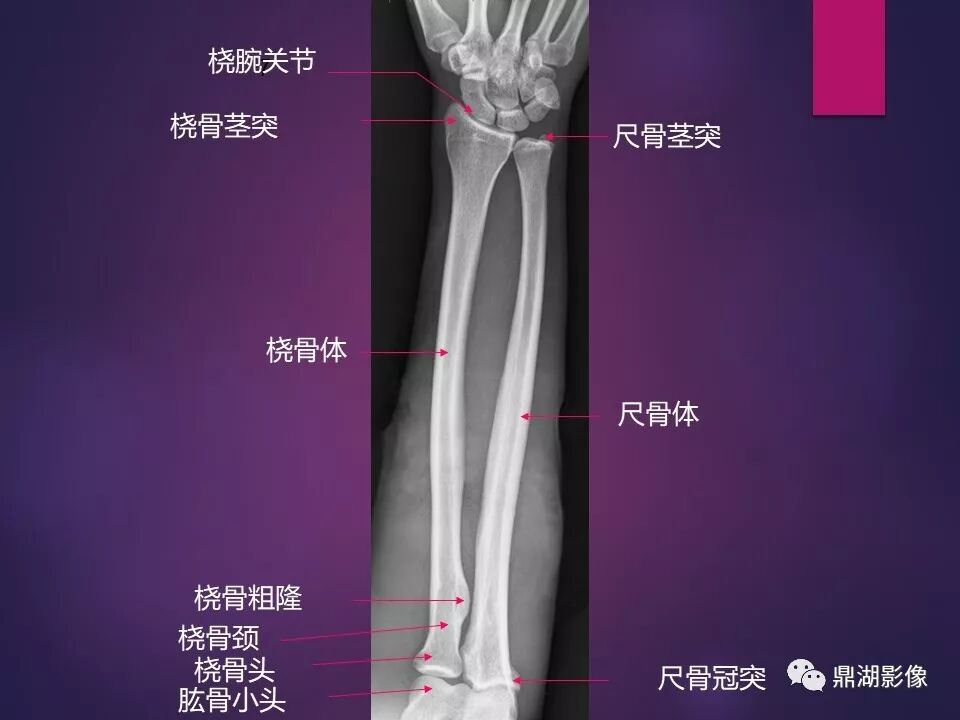

来源于:鼎湖影像 贵阳医学院医学影像系